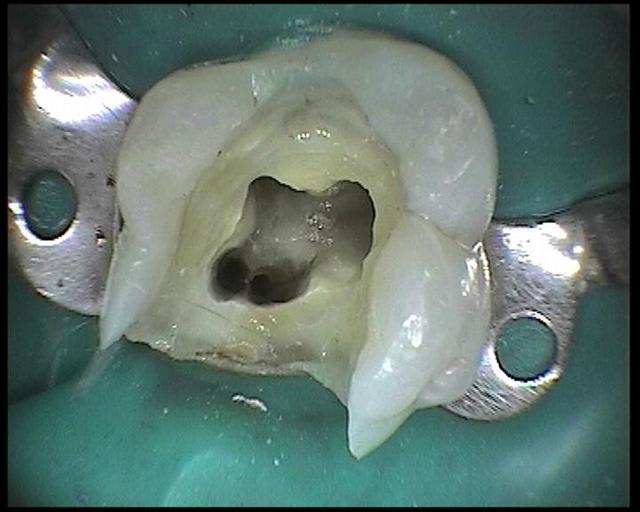

voici les images prises avec la sopro 595

Images en vrac de sopro 595